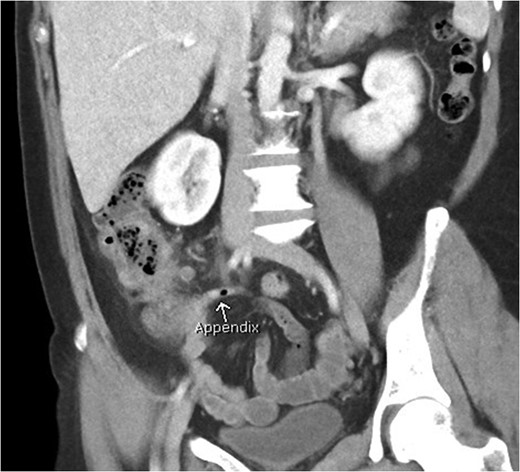

Coronal view of patient with caecal carcinoma. Normal (non-dilated) appendix (arrow).

Coronal view of patient with appendicitis. Dilated and thick walled appendix (arrow).

Axial view of patient with appendicitis. Eccentric caecal wall thickening (maximal surrounding the appendiceal orifice) with layered mural contrast enhancement secondary to prominent submucosal oedema (arrow) and prominent pericolic fat stranding represent the CT manifestation of the surgical phlegmon.

Appendicitis features include a fluid-filled dilation (>6 mm) and thickening of the appendiceal wall with mild-to-moderate peri-appendiceal fat stranding [5]. Peri-caecal inflammation may occur, characterised by segmental eccentric bowel wall thickening centred over the appendiceal orifice. Importantly, the submucosa (expanded and low density), muscularis and serosa (both slightly thickened and enhancing more than normal) may be delineated in a stratified or layered pattern. Other complications may be present such as perforation or abscess formation, which are seen as rim enhancing collections. Rarely, hepatic abscesses may be present as a manifestation of portal pyaemia, characterised by diffuse liver lesions close to the portal vein tributaries.